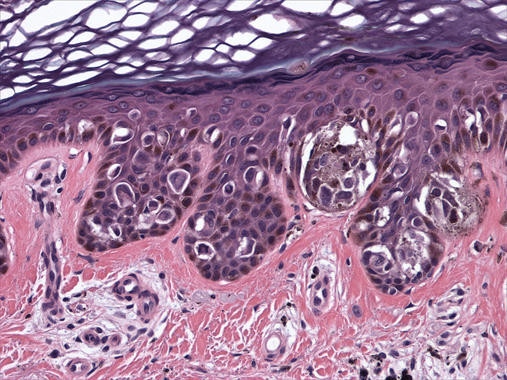

Un equipo internacional dirigido por investigadores españoles ha descubierto un nuevo tipo de fármaco con un potente efecto antitumoral en modelos animales de cáncer colorrectal y melanoma. Varias compañías se han interesado en el compuesto para estudiar sus posibles aplicaciones como terapia antitumoral en humanos.

“Hasta la fecha, se ha comprobado la eficacia de DEL-22379 en modelos animales de cáncer de colon y de melanoma, pero también se ha empezado a ensayar para cáncer de tiroides, pulmón y páncreas”, añade.